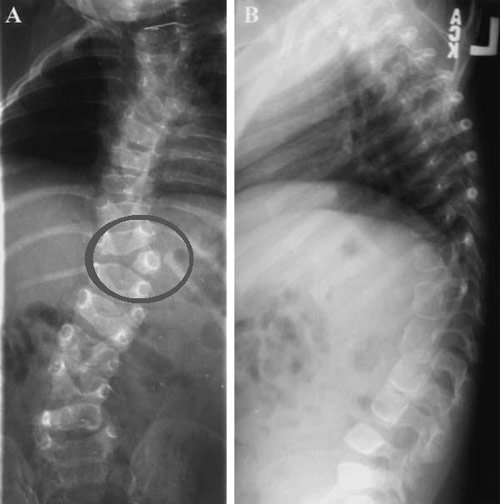

Сегментированный позвоночный столб (неполный блок позвонков) формируется при частичном слиянии боковых частей нескольких позвонков. Патология ведет к неминуемой деформации позвоночника, которую можно предупредить операциями c вживлением „растущей” металлической конструкции до периода полового созревания. Лечения корсетами не эффективно.